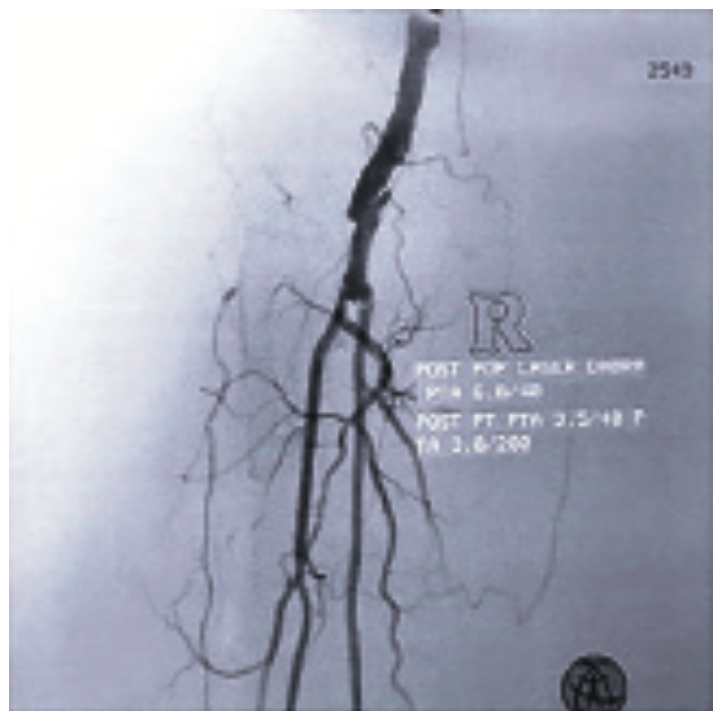

The small nub of the right posterior tibial (PT) extended only about 2-3 mm, with no runoff to the right foot. We initially attempted to cross the eccentric dissection at the level of the right popliteal artery to get into the true lumen using multiple wires, but were unsuccessful. Every wire we attempted went into the flap of the dissection. At that point, we elected to use the Destruction of Arteriosclerotic Blockages by laser Radiation Ablation (DABRA) catheter and laser (Ra Medical), a non-thermal excimer laser system that received FDA market clearance in May 2017, to ablate near the severely stenotic area in the P2 section of the popliteal artery. We made three passes with the DABRA, with the help of a 6 French (Fr) x 90 cm supportive sheath. The DABRA made the turn and stayed in the true lumen, making a small channel by ablating the plaque very close to the dissection without causing further dissection, in what is described as micro-plaque ablation. DABRA allowed us to perform accurate, precise plaque ablation around the dissection and resulted in a clear, smooth channel for laminar flow within the true lumen, enabling the 0.14-inch Glide wire (Terumo) to easily cross the critical stenosis at the level of the dissection. With a support catheter, the totally occluded PT was easily crossed and the wire was placed into the distal PT, followed by a 3.0 mm x 200 mm-long balloon inflated for three minutes. A 3.5 mm x 40 mm balloon was used to treat the ostium of the PT and the popliteal artery at 10 to 12 atmospheres for three minutes. Subsequently, the support catheter and wire were removed, and a small amount of contrast was injected, confirming we were in the true lumen in the distal PT.

Post procedure, the popliteal had <10 to 15% residual stenosis. The PT, which had been completely occluded, now had less than 10% residual stenosis and excellent in-line flow to the foot via the PT, with excellent flow in the plantar branches. The peroneal vessel, which previously had very poor flow, now had brisk flow all of the way to the ankle. The AT was intermittently seen with a faint visualization of the right dorsalis pedis vessel.